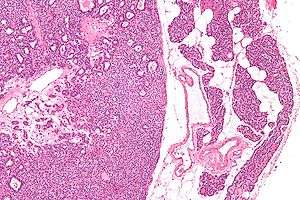

Micrographs of parathyroid adenoma